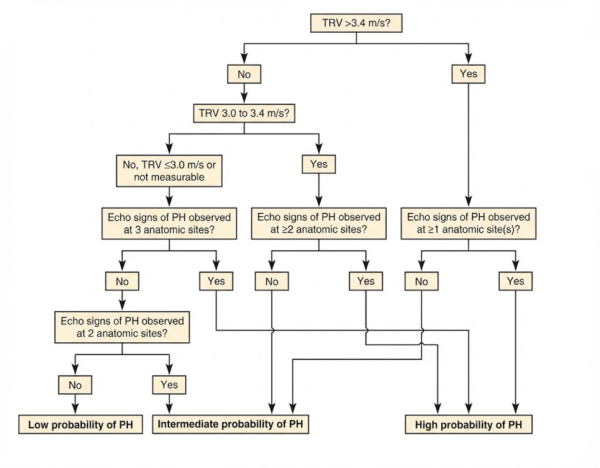

종합 판단: 이 아이는 TR 속도가 3.4m/s를 넘고, 3가지 카테고리(RV, PA, RA)에서 모두 PH 관련 징후가 나타나

ACVIM 기준 '폐고혈압 가능성 높음(High Probability)' 그룹으로 진단되었습니다.

어떤 원인에 의한 폐고혈압인가? (ACVIM Group 감별 진단)

단순히 "폐고혈압이다"라고 진단하는 것에서 그치지 않고,

ACVIM PH Consensus에서 권고하는 알고리즘에 따라

이 아이의 상태를 일으킨 근본 원인을 추적(Group Classification)해 보았습니다.